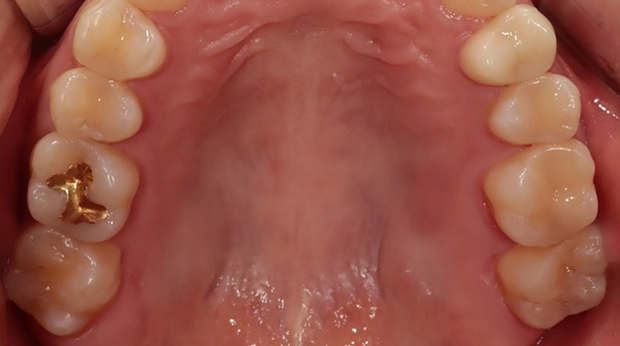

구강외과 진료

라미네이트

매복 사랑니 발치